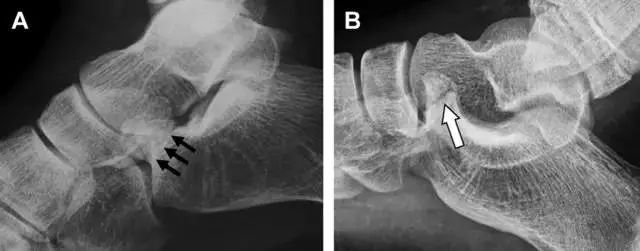

22

跗跖关节复合体(Lisfranc 关节复合体)损伤

与跗跖关节韧带相关的骨折常由旋前或旋后的跖屈损伤引起。尽管跗跖关节骨折脱位仅占所有骨折的 0.2%,但是约 20% 的这些骨折在初次检查时被漏诊。初次 X 片可能示正常,但是负重位 X 线片常常提示脱位或半脱位。

典型表现:第二跖骨底和内侧楔骨之间的骨折碎片,跖骨间间隙增宽(图 8)。脱位亦可发生在舟骨-内侧楔骨关节,导致另一种变异的跗跖关节损伤(图 9A)。此外,骰骨的小块皮质撕脱在足部斜位片上可清晰显示(图 9B)。

图 8 从马上摔落的患者,跗跖关节骨折。A 正位片示内侧楔骨旁边的小骨折碎片(箭头),第二跖骨底向外半脱位;B 负重位侧位片示第二跖骨相对中间楔骨向背侧轻微移位(长方形);C STIR 序列 MRI 图像示跗跖关节韧带断裂(箭头),第一至第三跖骨、内侧楔骨及中间楔骨均骨髓水肿。

图 9 变异的跗跖关节骨折。A 另一种类型的跗跖关节损伤,中间楔骨向内侧半脱位(弧形箭头),从而使第一、第二跖骨间间隙变宽,需关注,骨折在靠近内侧楔骨处(箭头);B 外侧跗跖关节损伤伴随从骰骨跖骨韧带的骰骨撕脱(箭头),需关注,第五跖骨底近端处存在软组织水肿(空箭头)。